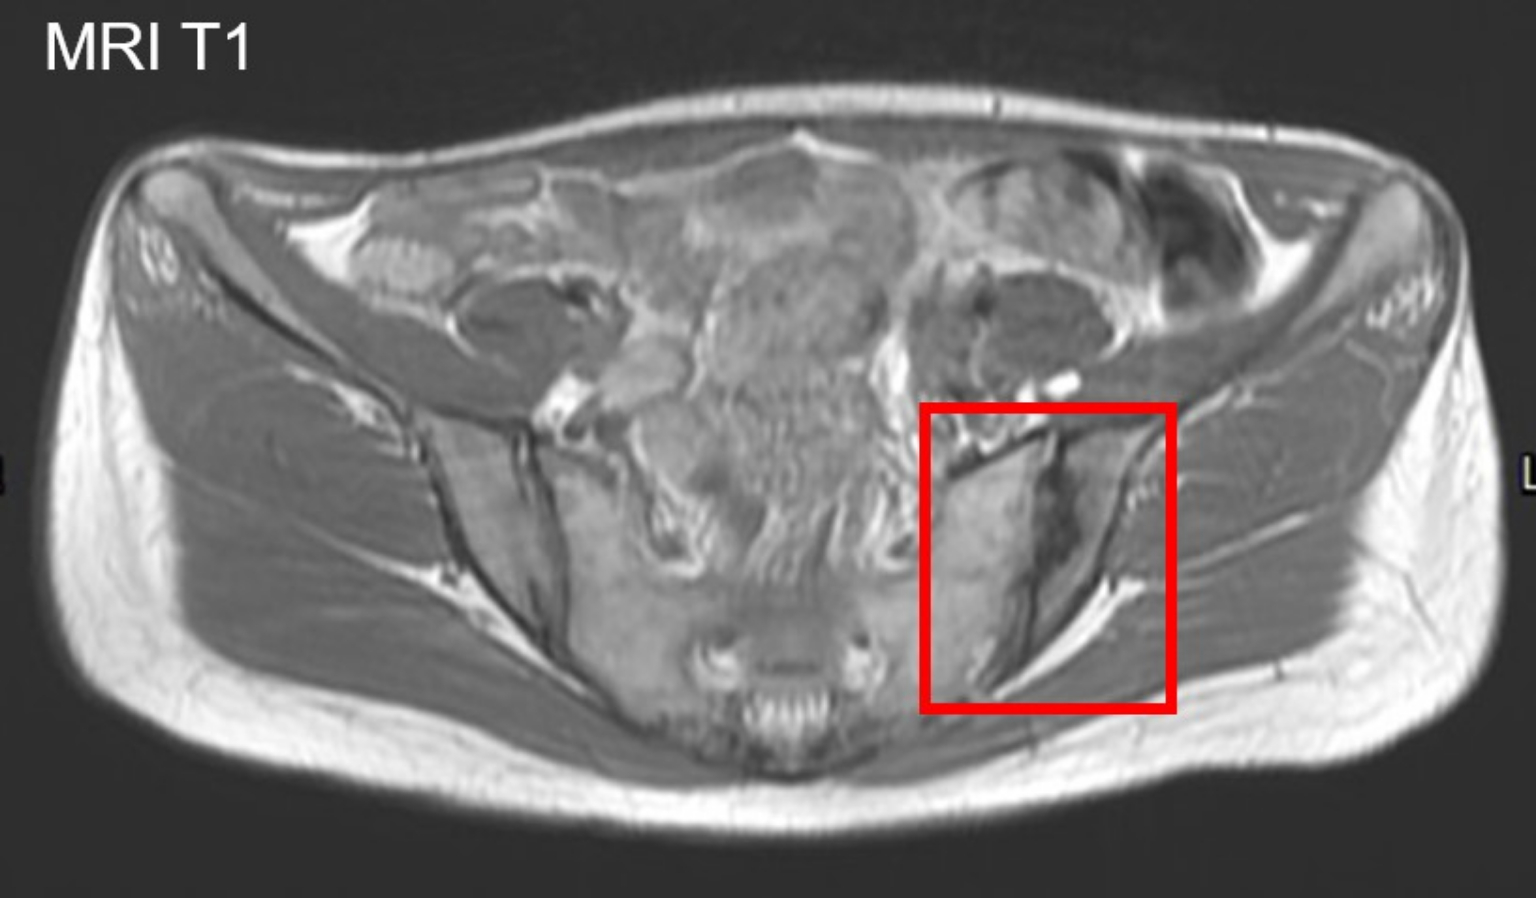

盧俊吉表示,僵直性脊椎炎影像學診斷標準,包括X光片顯示薦腸關節兩側第2度或是單側第3度以上發炎,以及核磁共振成像(MRI)顯示薦腸關節骨髓發炎。傳統利用X光片檢查僵直性脊椎炎患者,僅能看到患者的發炎程度在兩側第2度以上,或是單側第3度以上,並合併上述提到的早晨睡醒後下背僵硬、皮膚乾癬、手指關節、腳後跟紅腫痛等症狀。

根據三軍總醫院風濕免疫過敏科的研究顯示,MRI可以檢測早期僵直性脊椎炎患者的薦腸關節慢性發炎引發的骨髓水腫和結構損傷,而X光片僅能顯示結構損傷,尤其可以使用於亞洲患者的早期診斷。

盧俊吉指出,第1度和正常其實不太好分,但透過MRI可以提早發現是否有早期發炎,也可以看到骨頭是否有水腫的現象,以及協助診斷下背痛但發炎指數皆正常的早期僵直性脊椎炎病患。「不過重點還是患者要先有症狀,有些像喜歡跑步的人、孕婦、軍人...做核磁共振都發現有異常,有時候其實是過度診斷,所以病人一定要有症狀。」

三總的研究顯示台灣僵直性脊椎炎患者具有較少的骨髓水腫,「我們運用常規X光片檢查及MRI來幫助正確並早期準確診斷僵直性脊椎炎病友的早期薦腸關節炎和結構變化。」他也提到,僵直性脊椎炎如果不去管他,破壞會越來越明顯,「到後面會變成脊椎僵硬、沾黏,腰痛到半死也不能動。」